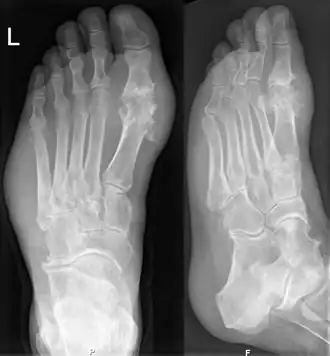

Jicht kan bij iemand met hyperurikemie en de klassieke podagra worden gediagnosticeerd en behandeld zonder verder onderzoek. Als aan de diagnose wordt getwijfeld, moet de gewrichtsvloeistof worden geanalyseerd.[1] Röntgenfoto's zijn nuttig voor het herkennen van chronische jicht, maar zijn nauwelijks van nut bij acute aanvallen.